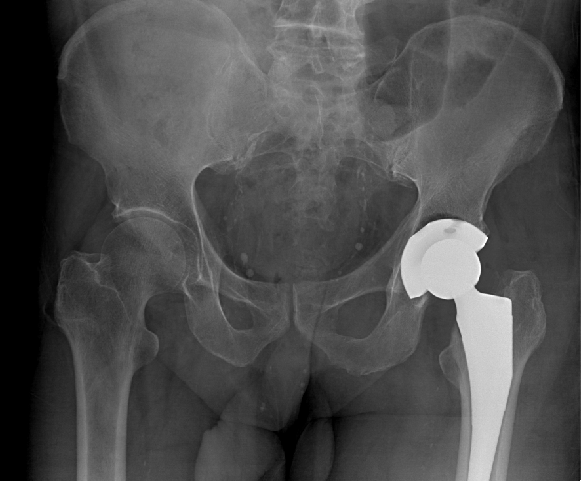

微创后入路径全髋关节置换术后X光片

作为全球首创快速康复的髋关节置换微创技术,微创后入路全髋关节置换技术是近年来人工髋关节置换技术的一大飞跃,与传统的髋关节置换技术相比,该技术利用5-7厘米的小切口进行人工髋关节置换,利用肌肉间隙入路,避免了传统髋关节手术对外旋及外展肌的损伤,最大程度保留关节囊完整性。由于完整保留了外旋肌群和关节囊,术中及术后关节脱位风险大大降低,术中的出血和组织损伤较少,手术出血一般在100ml左右。患者术后无需行特殊体位和活动度的限制。在术后4-24小时即可实现下地活动,因此大大降低了血栓发生风险。患者快速进入康复训练,缩短了患者住院时间、减轻了患者家庭和社会负担。

微创化一直以来都是骨科医生团队不断探索的目标,而微创后入路全髋关节置换手术(Superpath)实现了真正意义上的微创,不仅是一种全髋关节置换新技术,更是一种“快速康复”的新理念。该技术有损伤小(肌间隙入路)、术口切口小(5-7厘米)、出血少(100毫升左右)、下床活动早(4-24小时即可下床训练)、疼痛轻(术后无需使用止痛泵)、住院时间短、住院费用少、无脱位风险、康复出院快、患者满意率高等优点。因此,深受医患广泛好评。